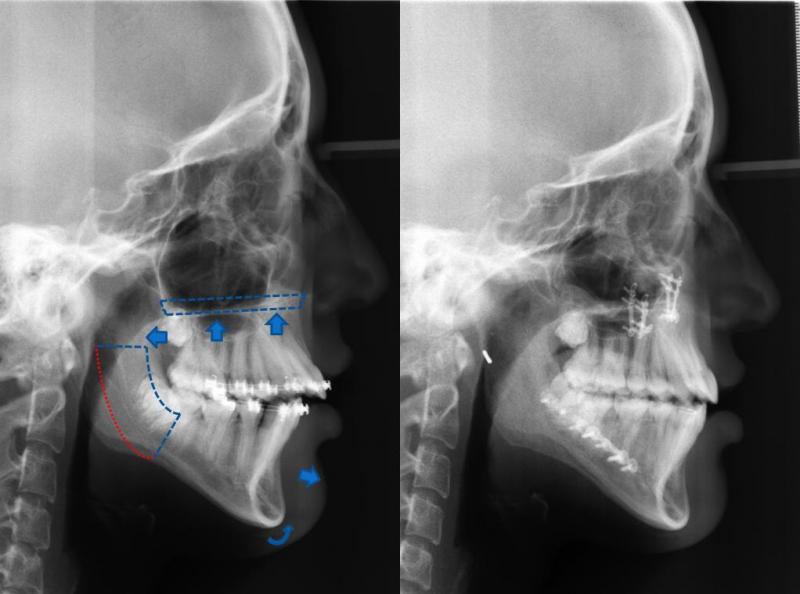

Ortodontiyle dişlerin yeniden konumlandırılması mümkün olduğu gibi ortognatik cerrahi ile de büyüme gelişimlerini tamamlamış erişkin hastalarda ki çene uyumsuzlukları düzeltilebilmekte, çiğneme, konuşma, soluk alma fonksiyonları iyileştirildiği gibi yüz görünümü de güzelleştirilebilmektedir.

Cerrahi öncesi 6-18 ay süreyle orthodontik hazırlık aşaması gerekmektedir. Bu aşamada dişlerinizin daha da kötüleştiğini düşünebilirsiniz fakat dişlerinizin konumları çenelerinizin ameliyat sonrasındaki konumlarına göre şekillenmektedir. Cerrahi sonrası çeneleriniz uygun konumlarına getirildiğinde dişlerinizin muntazam ilişkide olduklarını göreceksiniz.

Son görüntüleme teknikleri kullanılarak ortognatik tedavi sonucu kişinin kazanacağı estetik ve fonksiyonel faydalar öngörülebilmektedir. Bilgisayar destekli tedavi planlaması ve diğer teknolojik gelişmeler, cerrahi işlemin etkinliğini artırmakta ve cerrahi sonrası iyileşme sürecini kısaltmaktadır. Böylece hastalar cerrahi sonrası rutin hayatlarına en kısa zamanda dönebilmektedirler.